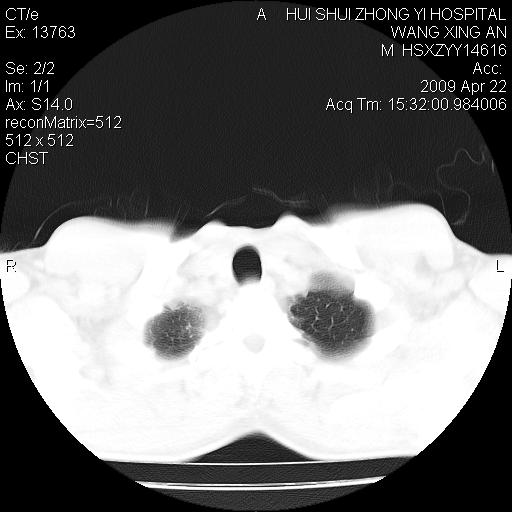

标题: CT19534:患者男、46岁咳嗽、胸痛半月。 [打印本页]

标题: CT19534:患者男、46岁咳嗽、胸痛半月。

1、右下肺中央型肺癌并右肺转移,右肺下叶不张。(肿块围绕右肺下叶支气管生长,致管腔闭塞右肺下叶不张;右肺有结节影)。

2、右侧胸腔积液。

3、右中上肺陈旧性肺结核(右肺见纤维化病灶及点状钙化)。

1)右肺中间段支气管癌并右肺下叶肺不张。2)右肺上叶、两肺下叶背段感染性病变。3)右侧少量胸腔积液。